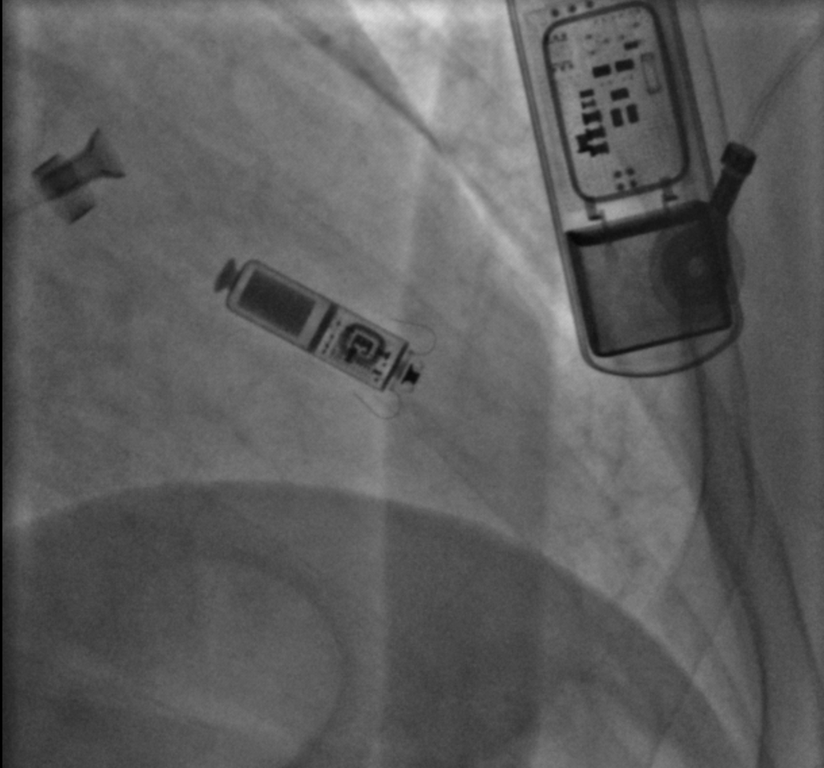

Il pacemaker di nuova generazione Leadless Micra A/V, ha le dimensioni di un euro e ricorda una pillola di antibiotico, una dimensione ben diversa del classico grande come due orologi da polso.

Il micro pacemaker, grazie ad un sistema “senza fili”, riduce, invece, sensibilmente le eventuali criticità: "impiantato tramite la vena femorale, viene introdotto attraverso un tubo della misura di un dito fino al ventricolo dove viene poi rilasciato e fissato tramite quattro ancore. Fino ad ora, però, presentava anch’esso un limite: fissato su un’unica camera ventricolare era in grado di agire solo sulla stessa, lasciando scoperto l’atrio. Il Leadless Micra A/V, al contrario, tramite un sensore, permette ora di mantenere la sincronia tra le camere garantendo con l’impianto di un solo apparecchio il corretto dialogo tra atrio e ventricolo.